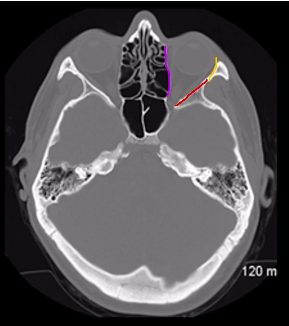

Q

what is

A

ethmoid bone - purple

sphenoid bone - red

zygomatic bone - yellow